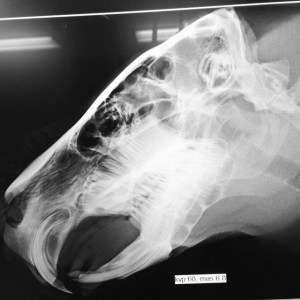

When his lower incisor became infected, I flew to Texas to be with Melanie for Gari’s surgery. Rodent teeth grow continually from a tooth bud, unlike our teeth, which are rooted into our jawbone. Gari’s jaw was so infected that the entire incisor fell off into the surgeon’s hand.

- Radiograph